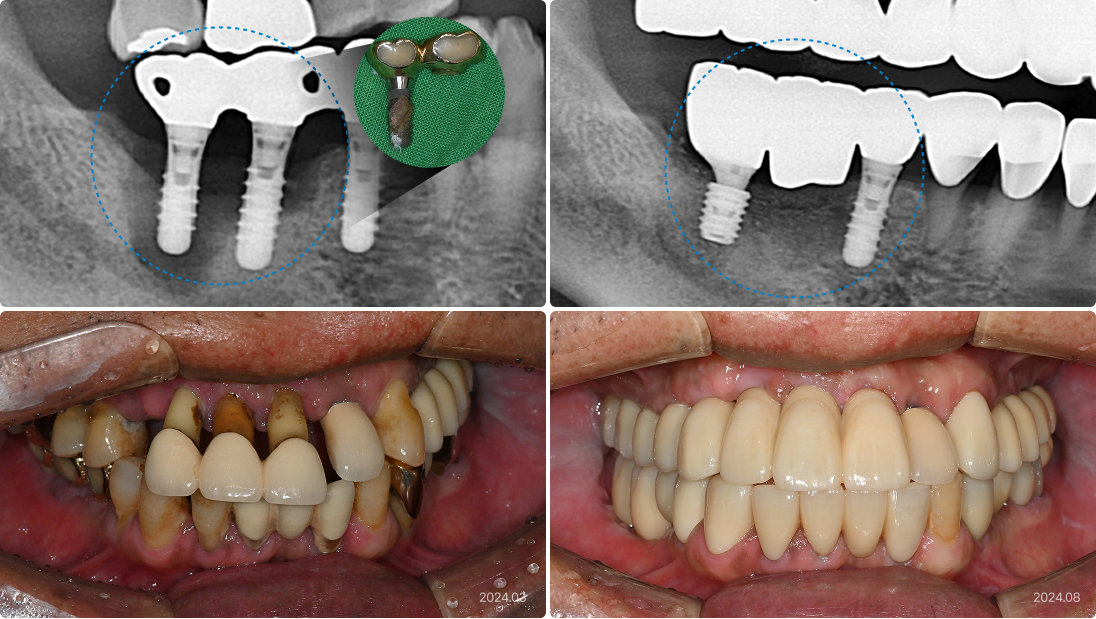

59세, 남 발치의 근본적인 원인을 해결하지 않은 채 임플란트만 진행

“큰 돈 들여 했던 임플란트가 아프고 냄새가 나요.

불편하지만 다시 하려니 경제적 부담이 커서 참고 있었어요.”

• 발치의 근본 원인인 치주염, 전신질환(당뇨)에 대한 개선책 없음

• 외산 임플란트를 필요 이상의 개수로 식립하여 지나친 비용 발생

• 오히려 관리가 어려워서 임플란트 주위염 악화됨

치료 후

• 오염된 임플란트 제거, 양호한 기존 임플란트 최대한 재사용

• 잇몸 염증의 치아 치료를 병행하여 염증 가능성 최대한 줄임

• 환자의 경제적 부담을 최소화하면서 치료 효율 극대화